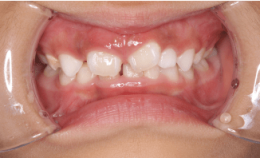

お子さまはどんな歯並びですか?

1.上顎前突(出っ歯)

上顎前突は、いわゆる出っ歯の状態で奥歯をかみ合わせた状態で、上下の前歯が離れて前後的な隙間がある状態のことを指します。

3.叢生(そうせい)、でこぼこ

叢生とは、歯並びがデコボコの状態のことを指します。